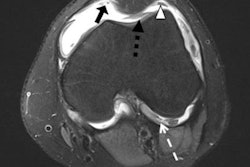

"Musculoskeletal ultrasound is booming in clinical practice for the diagnosis and evaluation of inflammatory lesions from inflammatory disorders, and it has been proved to be effective in the evaluation of bone erosions in various musculoskeletal diseases: osteoarthritis, gout, and psoriatic arthritis," the authors wrote. "In RA, many studies have shown that ultrasound can detect more erosions than x-ray at the joint level, especially at an early stage of the disease, with higher sensitivity and specificity than x-ray when a CT scan is taken as the gold standard imaging method."

The group conducted a study to assess ultrasound's performance in diagnosing erosive RA compared with osteoarthritis, tracking sensitivity and specificity. The research included 168 patients, 122 of whom had rheumatoid arthritis and 46 of whom had osteoarthritis. Of patients with rheumatoid arthritis, 32 had the disease less than two years ("early") and 90 had the disease more than two years ("late"). Patients were assessed for joint erosion, which was scored on six bilateral joints with a four-grade scale (metacarpophalangeal [MCP] joints 2, 3, and 5 and metatarsophalangeal [MTP] joints 2, 3, and 5).

On ultrasound, 95 rheumatoid arthritis patients (21 with early disease and 78 with late disease) and 12 osteoarthritis patients had erosive disease. Ultrasound had higher sensitivity values than x-ray, and a higher specificity value when it came to identifying at least two or more worn joints. It also had excellent agreement with x-ray for all joints -- both erosion on ultrasound of at least one erosion of grade 2 (92.8%) and at least two eroded joints (90.4%).